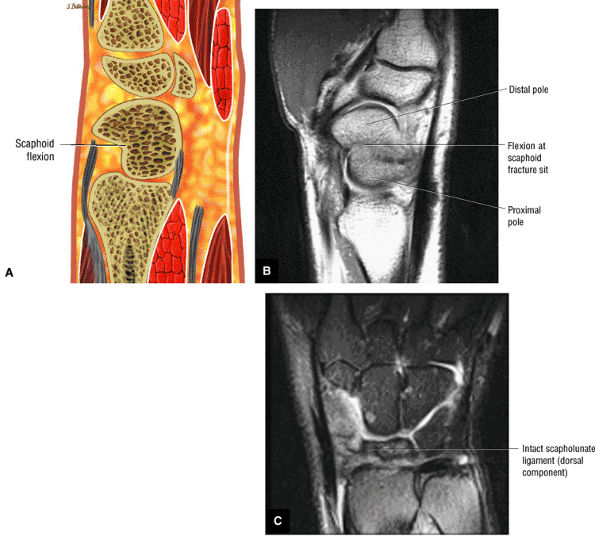

FIGURE 10.35 LUNOTRIQUETRAL LIGAMENT.

The lunotriquetral ligament is usually visualized as a thin horseshoe-shaped structure that may appear more lax than the scapholunate ligament on MR imaging.43 The lunotriquetral ligament does not extend as far distally into the lunotriquetral joint as the longer proximal distal portion of the scapholunate ligament does within the scapholunate joint.

The volar and dorsal portions of the lunotriquetral ligament attach directly to bone, whereas its midportion attaches to the hyaline articular cartilage of the lunotriquetral joint.43

Smith and Snearly53 have shown that on coronal MR images the lunotriquetral ligament is most commonly delta-shaped (triangular) or linear.